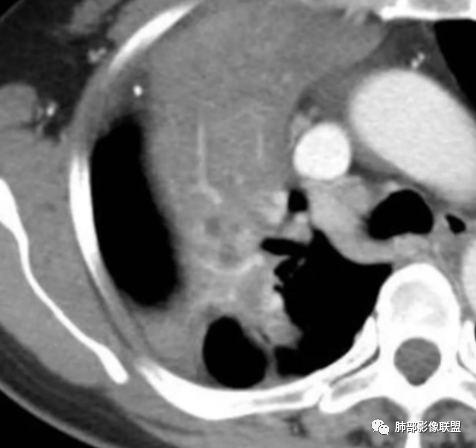

内部大片坏死区,其中还有不规则空洞

坏死腔内壁清,有强化环

肺动脉在实变区走形自然,坏死腔周围受压推移,走形自然,坏死区内破坏

这类坏死区内空洞,提示坏死液比较粘稠

不是液化坏死,液化坏死,这么大,有气体进来按理会形成液气平面

有脓腔,内壁光滑、强化环——支持感染

远端是不张合并感染